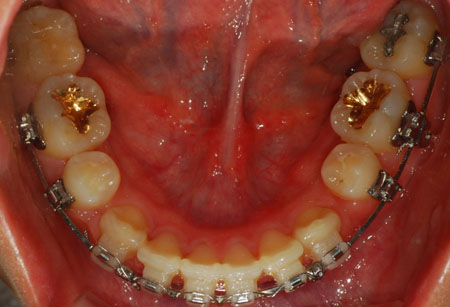

상악 사진

하악 사진